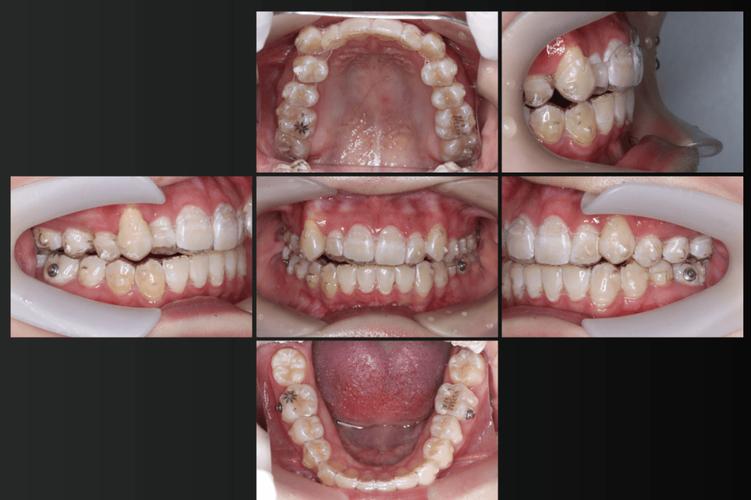

(图片来源网络,侵删) -